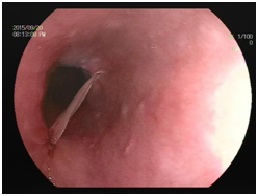

食物相关的异物:各种骨头、鱼刺、虾蟹贝的壳、枣核等尖锐的果核、坚果的果皮、大块没有嚼烂的食物等等,这一目录里的东西,大多数细嚼慢咽是不会误吞的。一些地区的饮食习俗也需要注意,如北方过年包饺子喜欢在里面放硬币,虽说寓意吉利,但吞进肚子或者硌坏牙齿的事故时有发生;南方的鱼丸、鱼糕等食品,制作时有时鱼骨难以完全去净,吃的时候还需要小心;喜欢煲汤的朋友们,处理食材时不要剁得过碎,喝汤时最后几口也是最容易卡到碎骨头的时候,而且这个时候一般已经吃饱喝足,来到医院胃镜是没法当时做的,需要等胃排空,只好整夜待在医院里留观,苦不堪言。在外面吃饭时更要小心,例如烤串的竹签劈裂下来的木刺、面条里的刷锅用的钢丝球、盒饭里方便饭盒掉下来的塑料片等等,这些都是真实发生过的教训。食物没有嚼烂卡在食管里的情况一般老年人相对多见,因为食物是可以消化的,可以尝试用胃镜把食团轻轻推进胃里。但是要注意,如果您平时细嚼慢咽,还是总觉得食物会卡住,一定要做个胃镜或钡餐检查一下,明确是不是食管本身出了问题。

图(2)这张图是胃窦,可以看到一枚枣核,顶端已经穿入胃壁中。正前方黑色圆形的孔是胃的出口——幽门